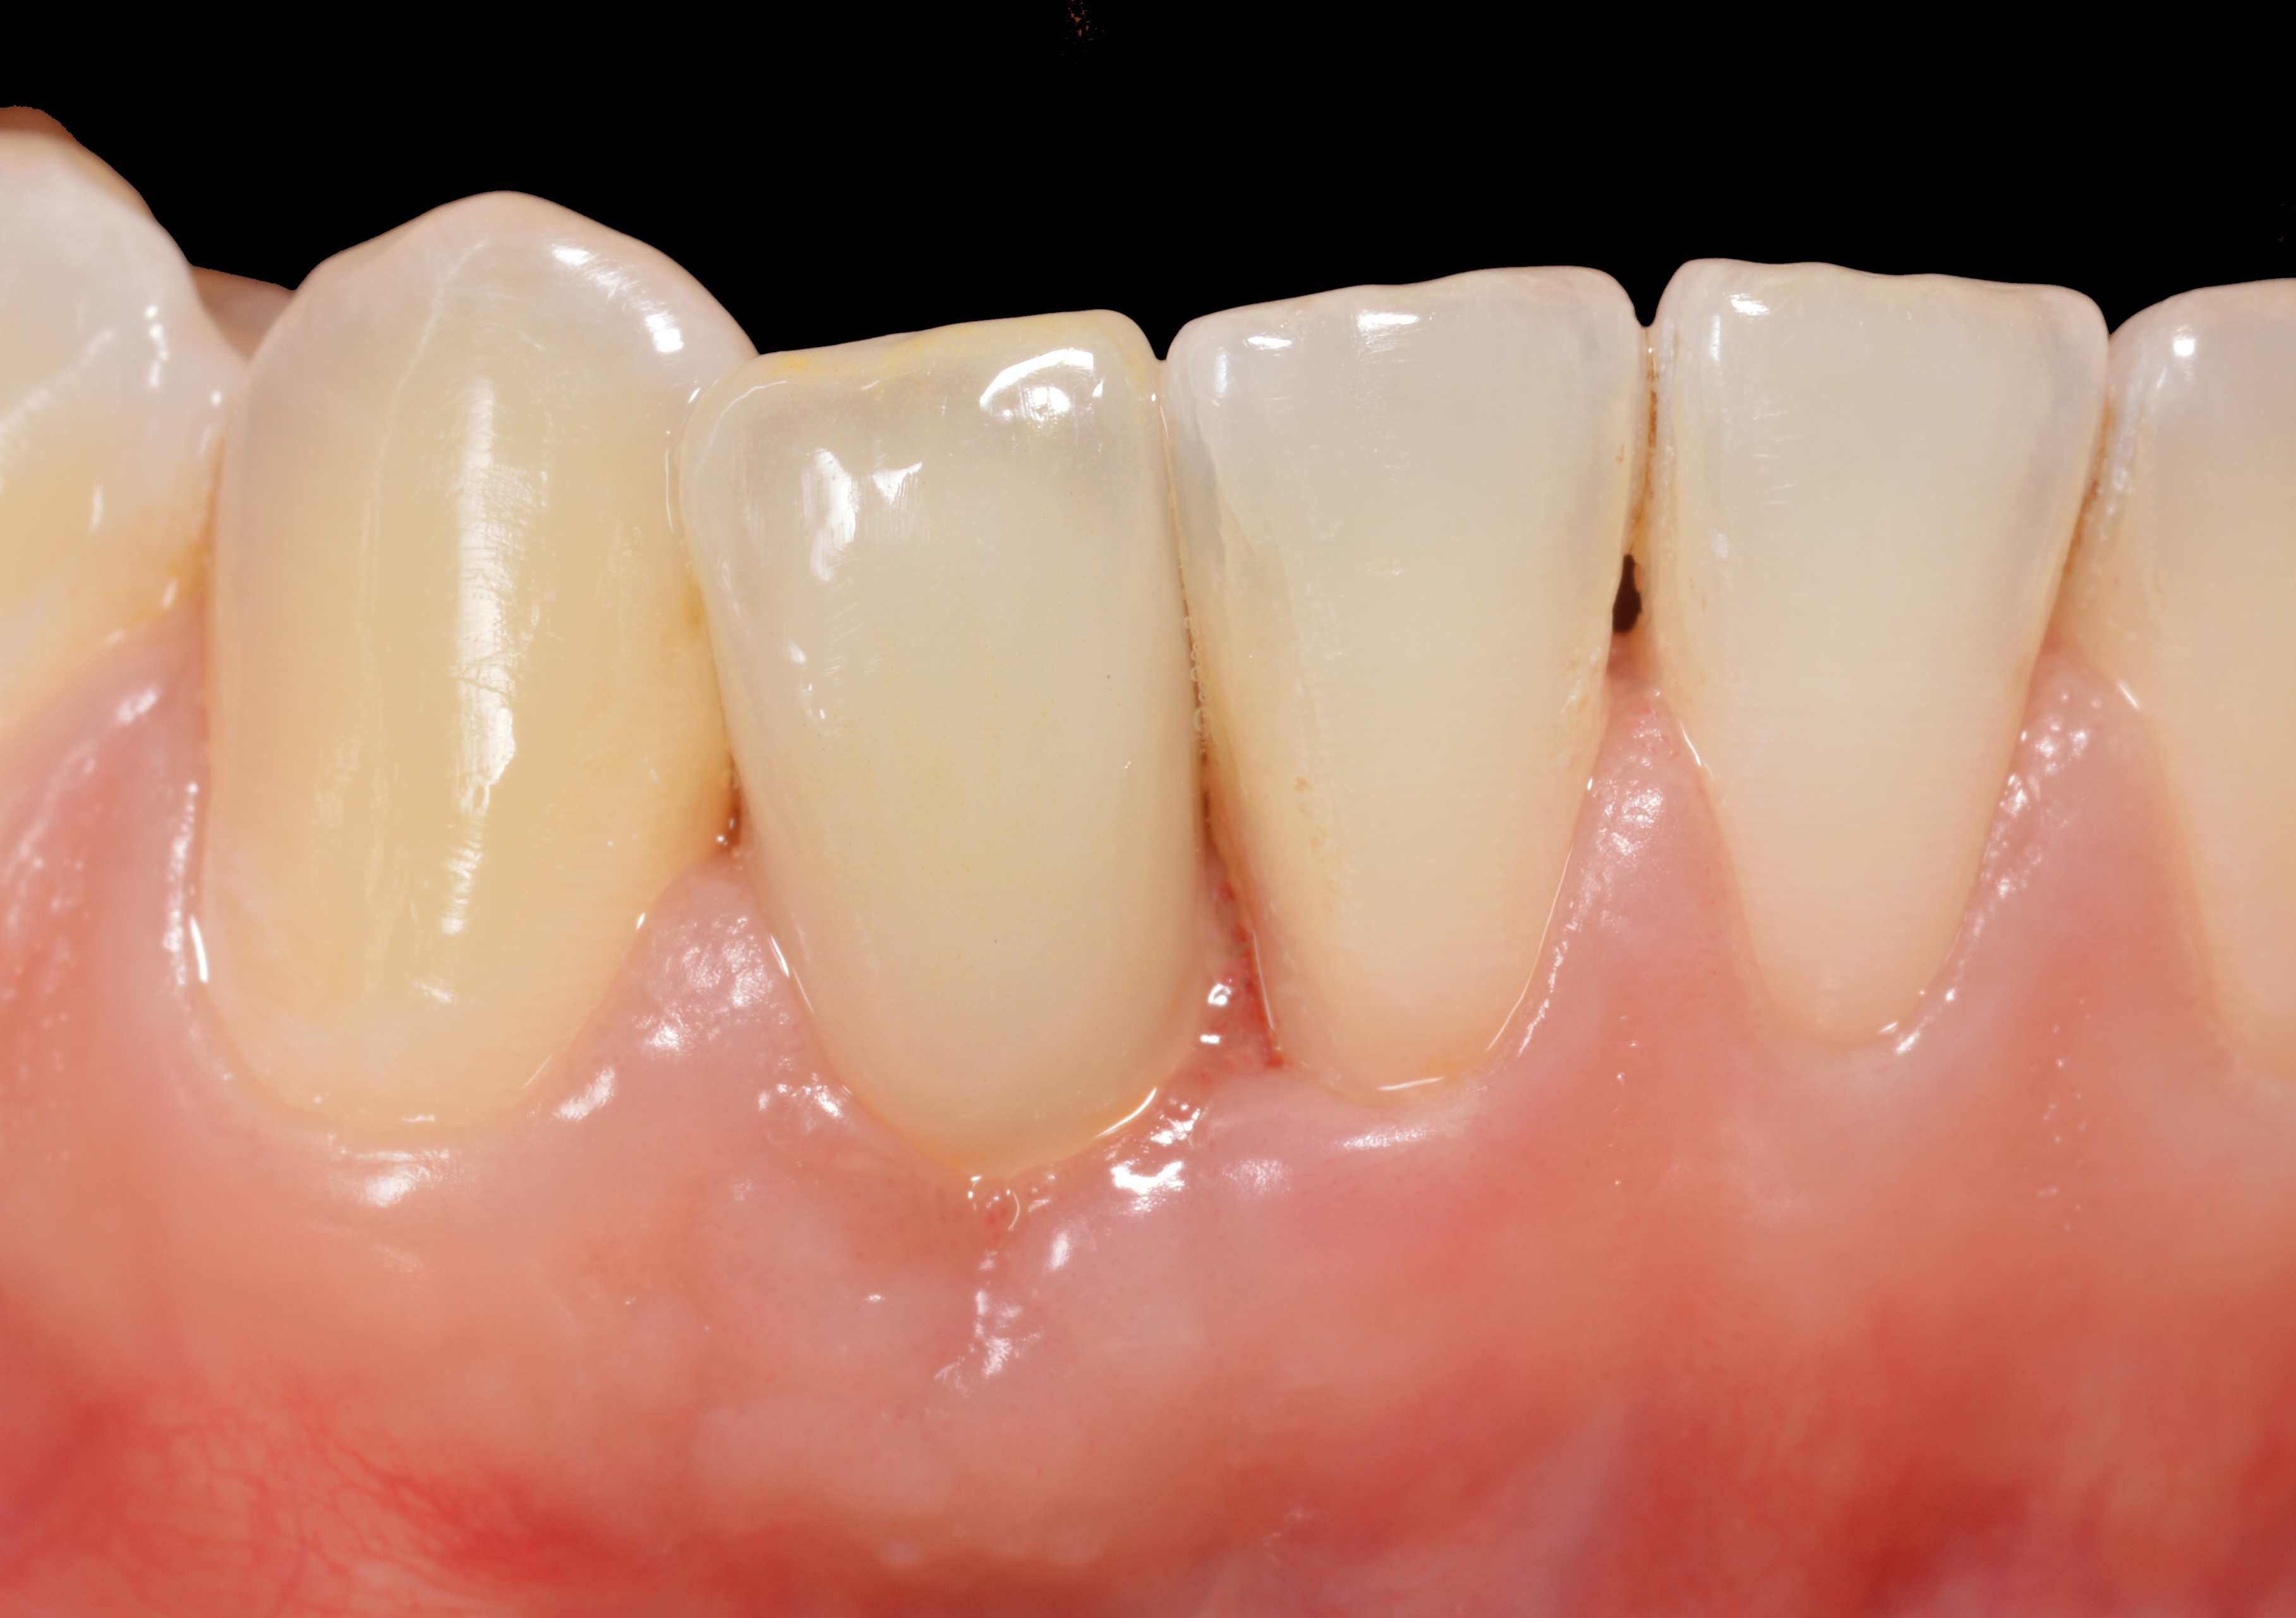

Fig 15. The implant-supported restoration of tooth No. 19 presented with a lack of attached keratinized gingiva, shallow buccal vestibule, and 2 mm of buccal recession.

Figure 15

Fig 16. The restoration exhibited an 8-mm pocket upon probing, with bleeding on the buccal aspect.

Figure 16